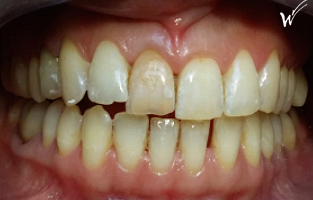

Cas clinique « SMILE RED FLAG MEI » : Traitement de remplacement d’une dent du sourire par un implant en Mise en Esthétique Immédiate. Visualisation de la version définitve de la couronne sur implant avec un cosmétique en céramique.

Situation clinique initiale avant traitement